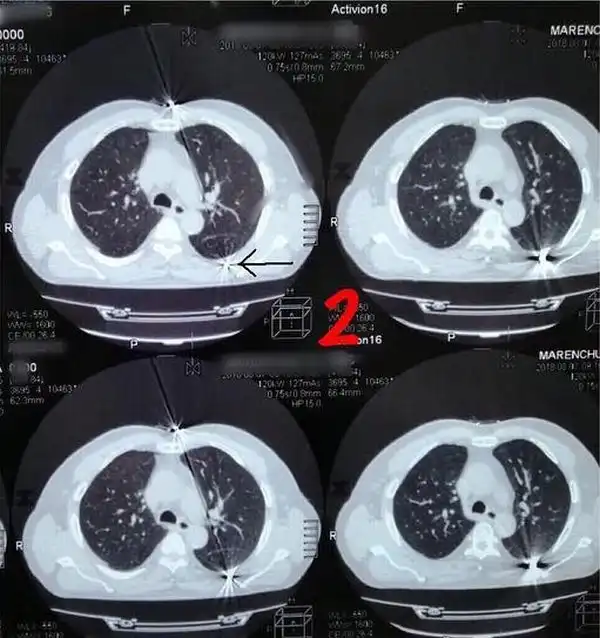

Врачи в Кабардино-Балкарии провели успешную операцию по извлечению пули из груди мужчины, который прожил с ней более 30 лет. По словам медиков, мужчина 1954 года рождения поступил в отделение с жалобами на ноющую боль в области груди, которая началась около месяца назад. Сделав рентгеновские снимки, медики обнаружили инородный предмет в грудной полости.

Как стало известно во время операции, инородным телом оказалась пуля. По словам медиков, она находилась в теле пациента уже более 30 лет, но начала создавать дискомфорт лишь некоторое время назад, когда сдвинулась с места.